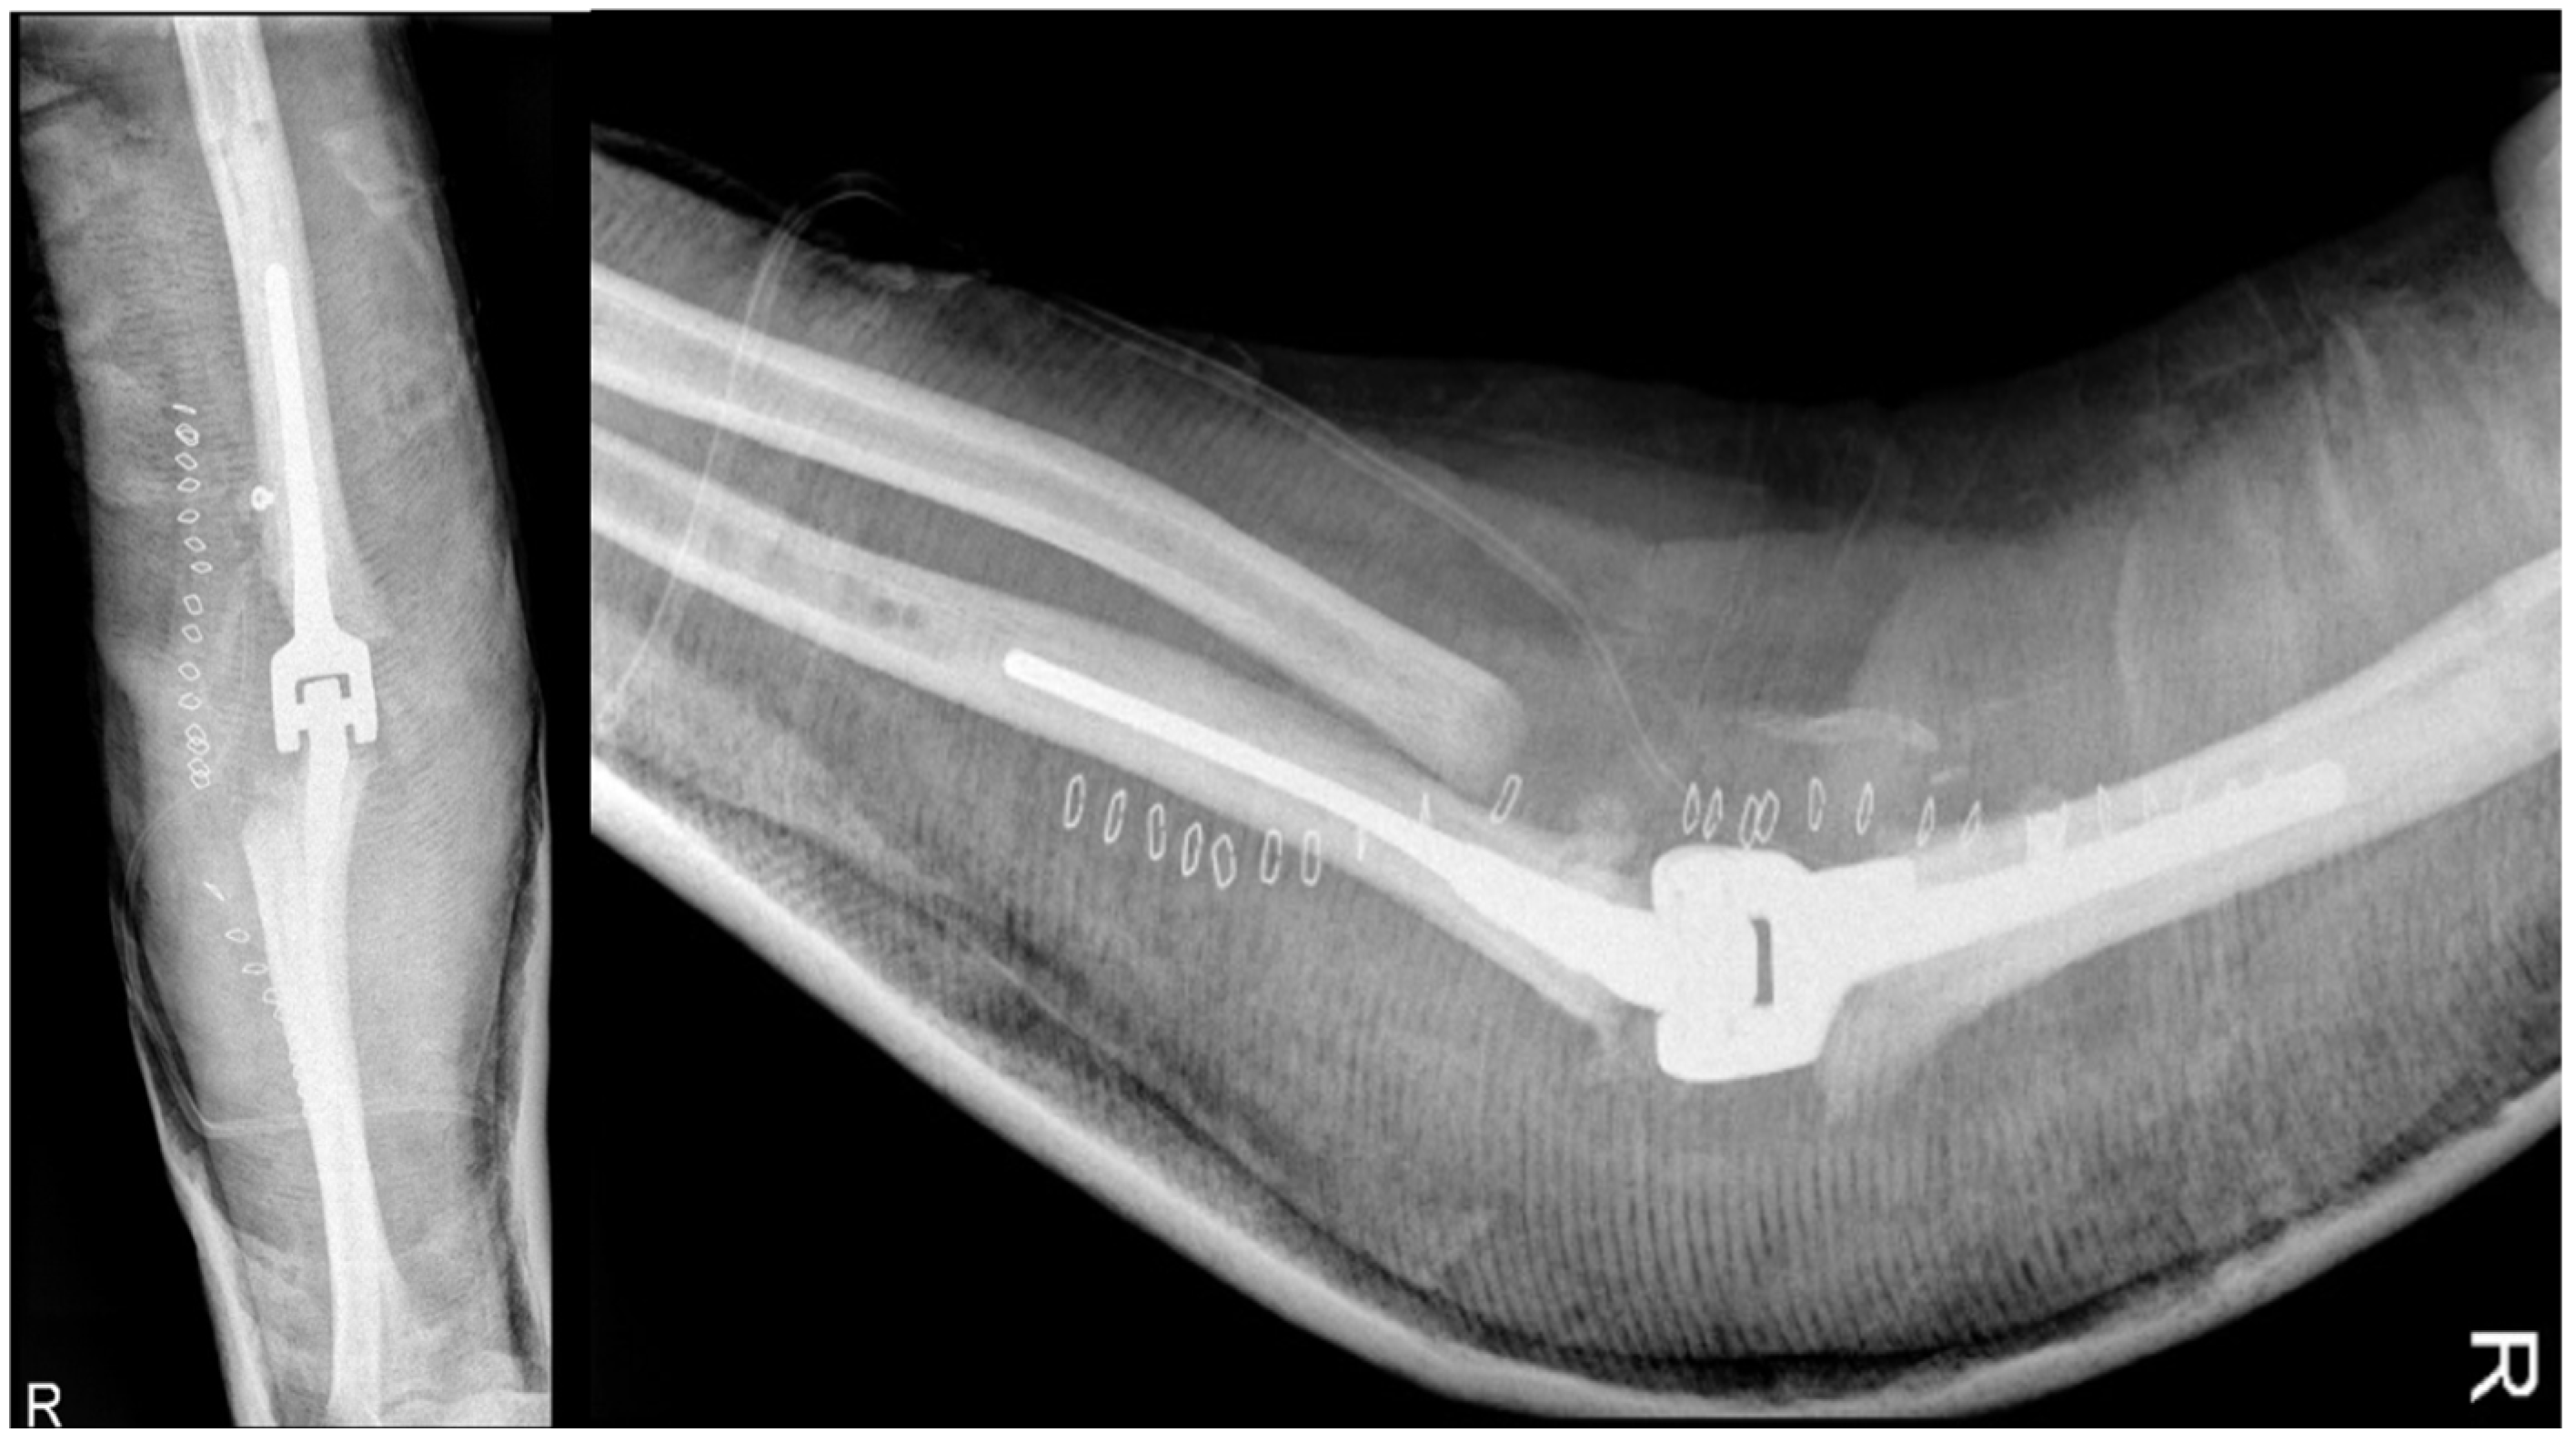

In August of 2013, a surgical operation was conducted to fuse the elbow joint using a plate with twelve holes and a ninety-degree flexion angle, utilizing the same surgical access point as the previous operation (as depicted in Figure 6). During the course of the procedure, the anatomical structures of the ulna, radial head, and distal humerus were significantly distorted and unidentifiable. New synovectomy and osteotomy were carried out to apply the plate. Following the patient’s release from the hospital, they were instructed to wear a brace at a ninety-degree angle and an arm sling, undergo physiotherapy to move the fingers and wrist, and undergo an X-ray examination thirty days post-surgery.

Figure 6.

Post-arthrodesis X-ray anteroposterior and lateral views of the right elbow. (a) Post operative images showing the plate in site. (b) Thirty days after images with mobilization of the synthesis with broken screws.

Arthrodesis and Complications

At the 30-day postoperative follow-up, radiography revealed three broken screws in the proximal humeral shaft and a subtle periosteal reaction around the plate. The patient was referred for fixation revision and was protected with a new brace. The screws and plates were removed using the previous lateral elbow access. However, internal fixation was not feasible due to the resemblance of the last 7–8 cm of the distal humerus to a cortical lamina. Consequently, an external fixator, bar-to-bar, was applied after the arthrodesis surfaces were prepared. as shown in Figure 7, the follow-up radiograph confirmed the appropriate positioning of the device. At hospital discharge, the orthopedic recommendation was to wear the external fixator for 60 days, rest, and undergo weekly ambulatory assessments of local clinical findings.

Figure 7.

X-ray anteroposterior and lateral views of the right elbow after the External Fixator positioning to stabilize the elbow joint.